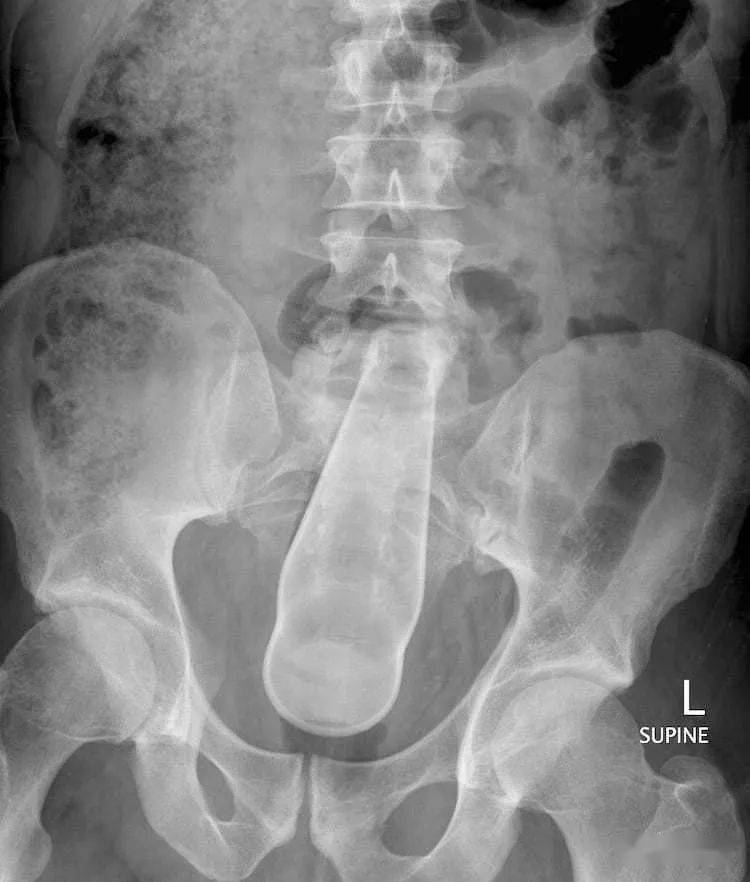

谁看了不说一句 , 人类真奇妙…最后 , 还有一个可以说最奇怪的故事 。一对同性恋人在一次啪啪啪过程中 , 决定尝试点不一样的新刺激 , 于是一个人躺下 ,让另一个人用漏斗把液态水泥倒进了肛门 。水泥不能长时间保持液态 ,当水泥硬化后 , 它就变成了巨大的水泥团 , 必须要手术才能清除 。